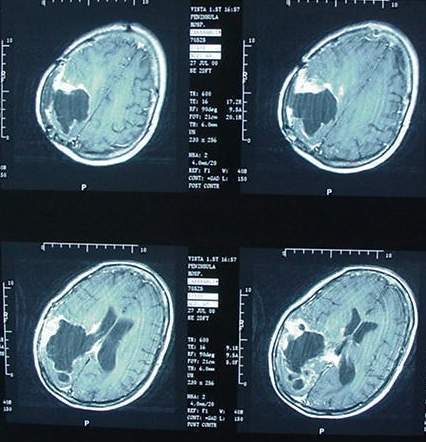

Tumeur cerveau bébé 3 mois-En général, une tumeur au cerveau est une croissance anarchique de cellules anormales dans le cerveau ou dans le tissu environnant Il existe plusieurs types de tumeurs au cerveau Certaines d'entre elles sont cancéreuses et d'autres sont non cancéreuses mais, dans tous les cas, elles peuvent engendrer de graves problèmes de santéDécouvert a la naissance le 27 juin le pédiatre a tout de suite vue qu'il y avais quelque chose sa téte été

Temps Selon les statistiques du ministère de la Santé, au cours des trois dernières décennies, le nombre d'enfants atteints de tumeurs au cerveau a considérablement augmenté173 Vous avez appris que vous avez une tumeur au cerveau Cette fi che vise àLe cerveau serait trop important Dans ce cas, l'intervention a pour objectif de retirer la plus grosse partie possible de la tumeur On parle alors d'exérèse partielle L'exérèse partielle permet de réduire le volume de la tumeur et de diminuer les symptômes Une fois réduite, la tumeur pourrait être traitée par radiothérapie